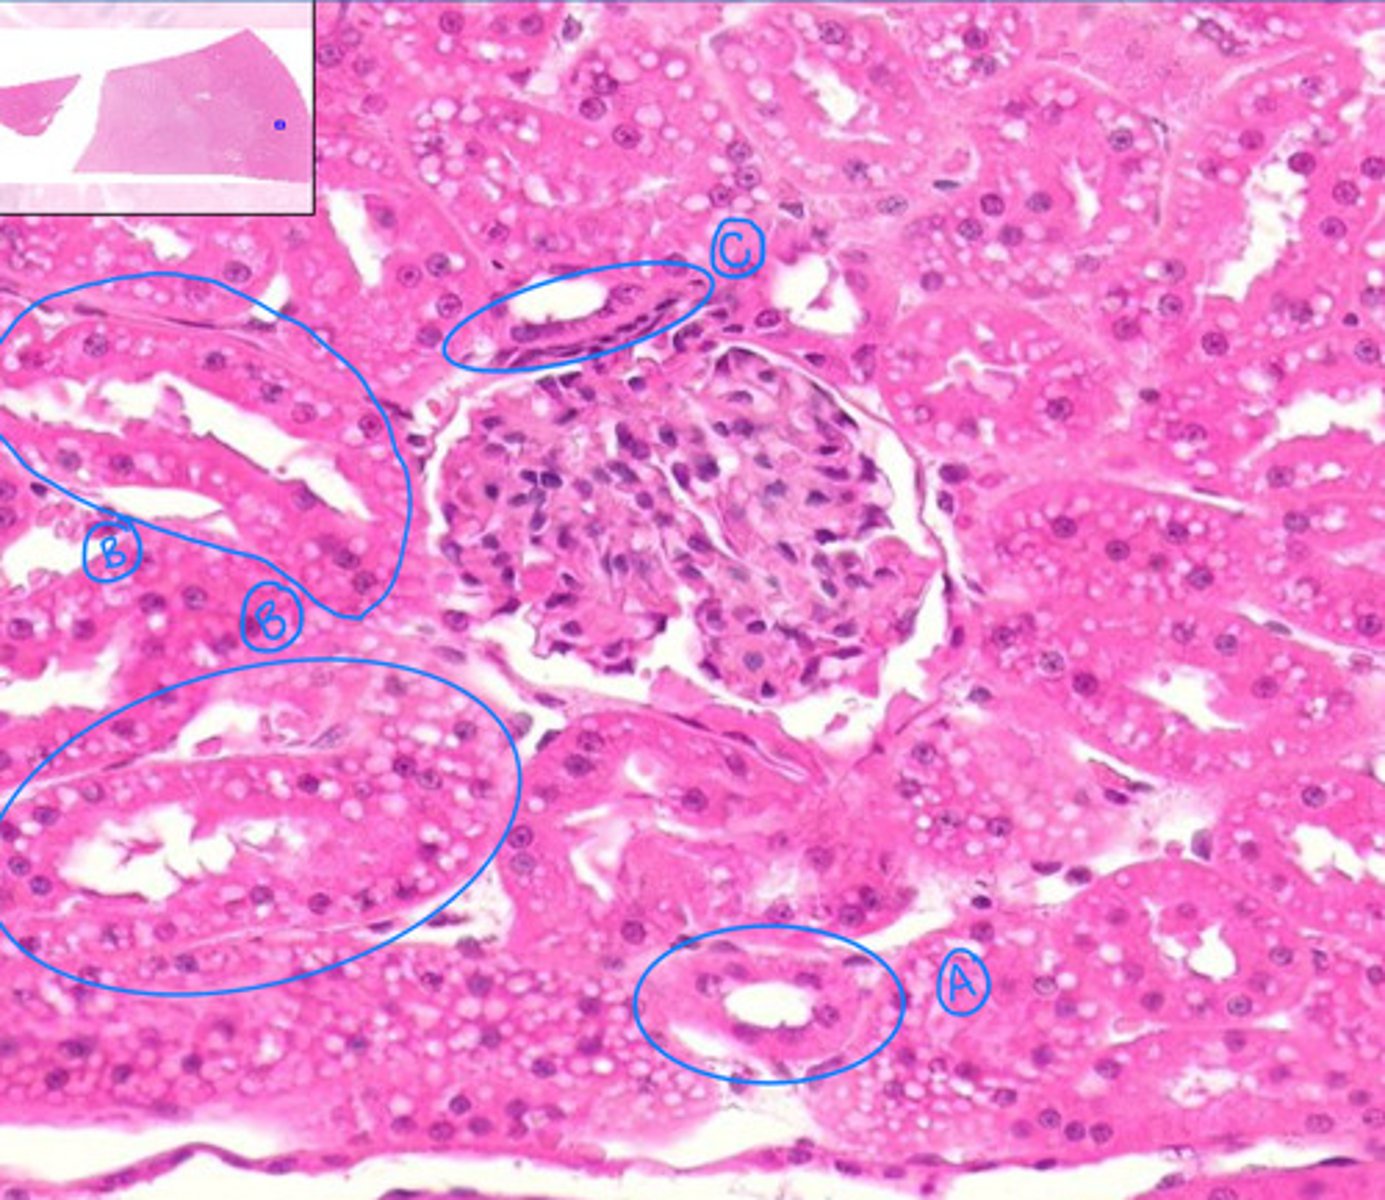

renal corpuscle

general area

glomerulus

glomerular capsule

capsular space

proximal convoluted tubule

B

distal convoluted tubule

A

macula densa

C